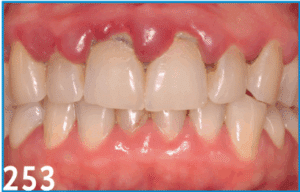

La prise en charge orthodontique des encombrements antérieurs chez l’adulte ne peut être dissociée d’une évaluation parodontale rigoureuse. Ce cas clinique illustre la nécessité d’une collaboration étroite entre orthodontiste et parodontiste afin de respecter les limites biologiques et de garantir la stabilité à long terme. Après un diagnostic complet incluant une classification parodontale selon les critères de l’EFP 2017, une stratégie thérapeutique conjointe a été établie : assainissement initial, apport gingival préalable, puis mouvements orthodontiques planifiés par setup numérique. Cette démarche intégrée a permis de restaurer l’esthétique et la fonction, tout en préservant le support parodontal. Le succès repose sur un suivi pluridisciplinaire et une communication constante entre les différents acteurs de soins.